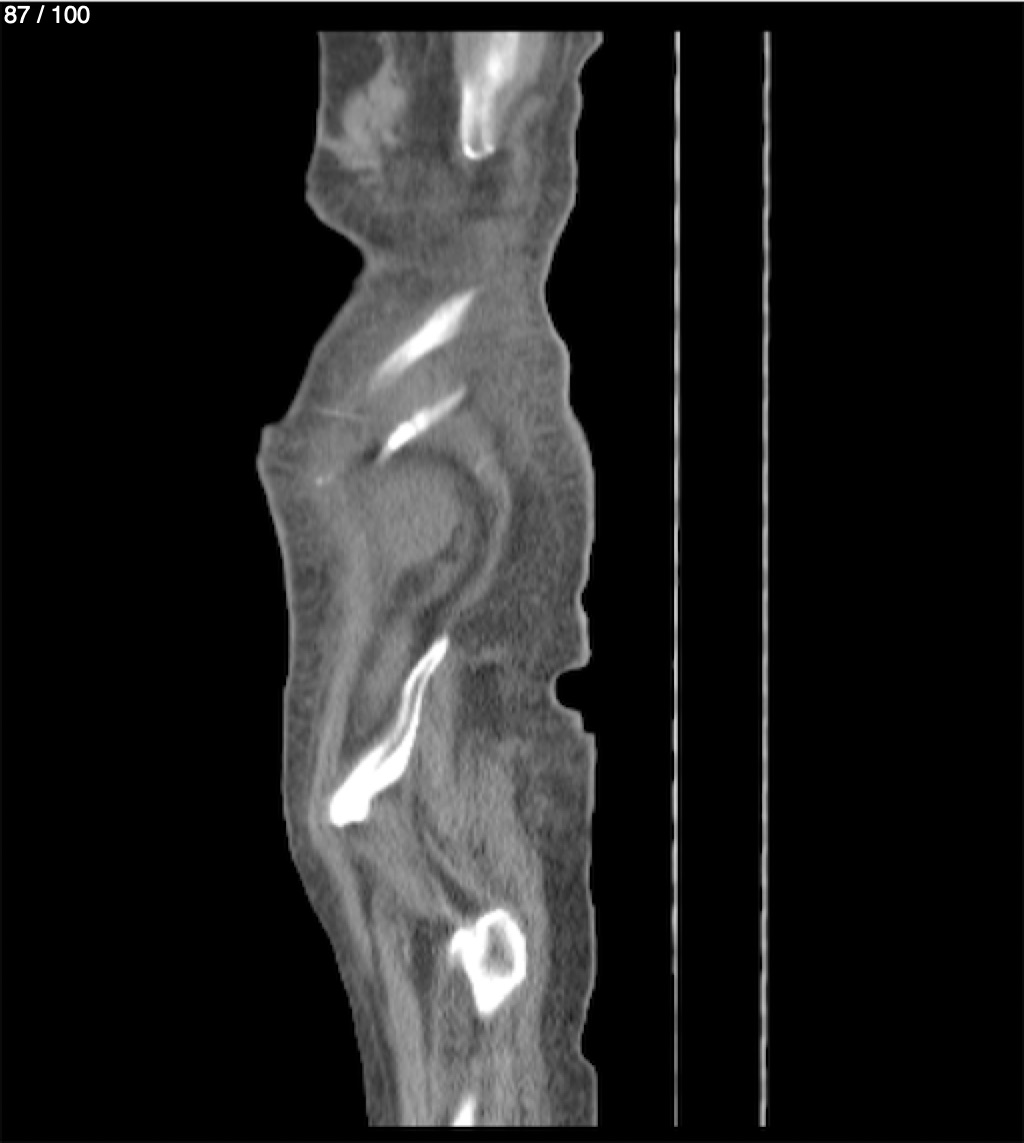

Hilda Geronimo Mendez 60A - T.C Abdomen Simple